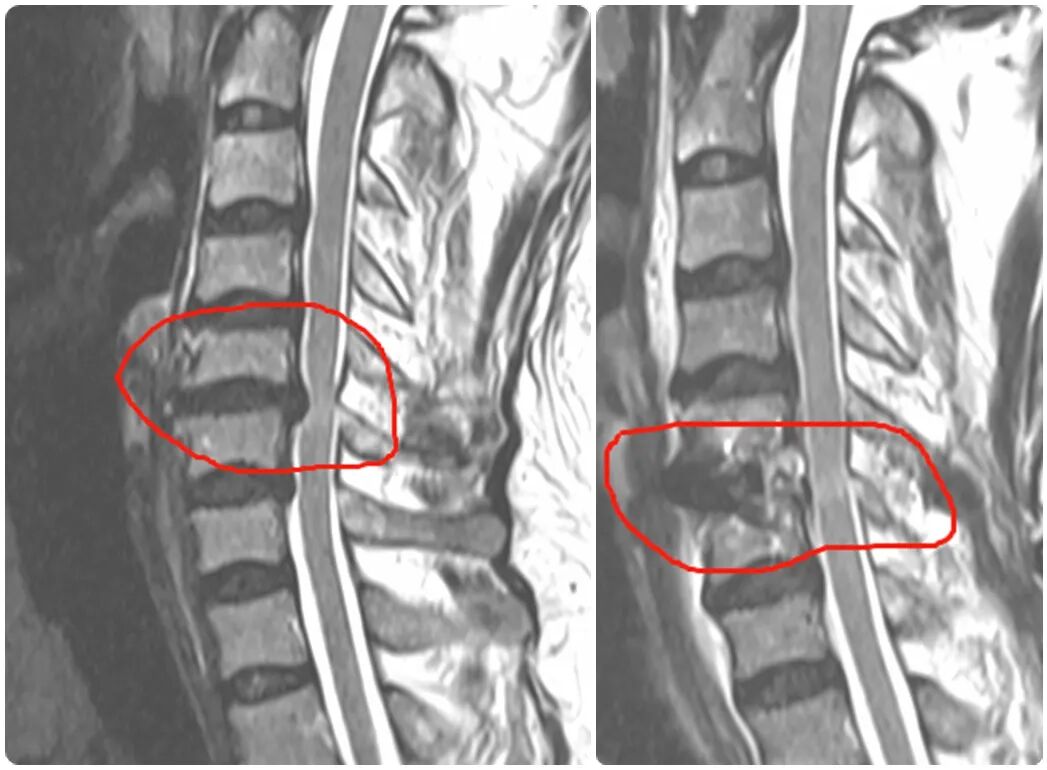

手術(shù)減壓前(左)、手術(shù)減壓后(右)